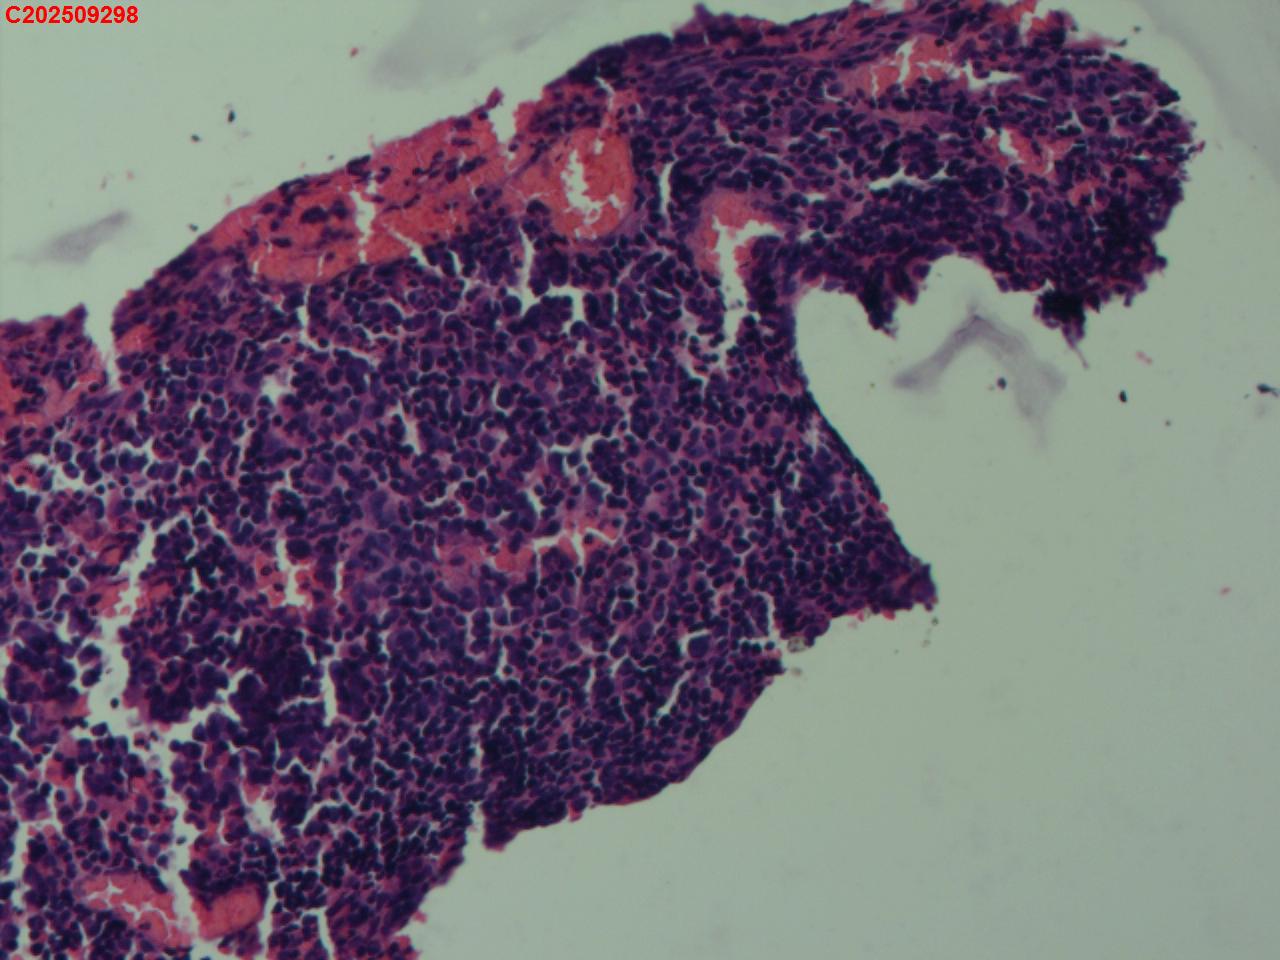

性别

女

年龄

34岁

临床诊断

胸膜结核瘤

一般病史

超声:可见右侧胸膜包裹囊性病变并见胸膜结核瘤。

标本名称

肺穿活检

大体所见

CT:胸部增强CT示右肺病灶局部增大,右侧胸腔结核性胸膜瘤可能。

送检组织·,镜下为炎性细胞和纤维组织。